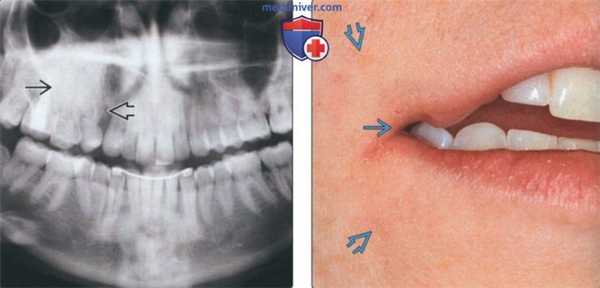

По результатам нашего исследования у 24 (14,5%) пациентов были обнаружены признаки хронического периодонтита в области премоляров и моляров верхней челюсти (рис. 1). Глубокий кариес был диагностирован у 4 (2,4%) пациентов, кисты верхней челюсти в области корней премоляров и моляров визуализировались в 6 (3,6%) случаях.

Рис. 1. КЛКТ. Панорамная (а) и мультипланарные реконструкции правого (б) и левого (в) верхнечелюстных синусов пациента М., 37 лет. Диагноз: двусторонний одонтогенный хронический верхнечелюсной синусит. Отмечаются КТ-признаки хронического гранулематозного периодонтита зубов 1.8, 2.7, 2.8 (в виде очагов деструкции у верхушек корней, округлой формы, с четкими ровными контурами). Нижние костные стенки синусов истончены, не прослеживаются в области периодонта зубов 1.8 и 2.8 (указаны стрелками). В нижнем отделе правого верхнечелюстного синуса определяется пристеночное мягкотканное образование гомогенной структуры с полицикличным верхним контуром. Левый верхнечелюстной синус субтотально заполнен мягкотканным содержимым гомогенной структуры с округлым верхним контуром.

(Слева) На кадрированной панорамной рентгенограмме у женщины 26 лет определяется повышение плотности альвеолярной кости в области премоляров верхней челюсти справа. Визуализируется просветление между первым моляром и клыком, подозрительное на расщелину. О наличии расщелин сообщалось и в других случаях заболевания. Оба премоляра отсутствуют.

(Справа) На фотографии у этой же пациентки видна расщелина угла рта на фоне гиперпигментации лица. Эти нарушения часто сочетаются с СВО. Также наблюдается гипертрихоз.